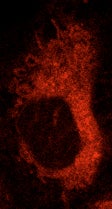

Investigating the mechanism of cellular responses to photosensitizers and light (photodynamic therapy, PDT), focusing on Pc 4, a phthalocyanine photosensitizer developed by our group, determining where Pc 4 binds in cancer cells, which membrane components are initially photodamaged, and how lethally damaged cells are eliminated by apoptosis or autophagy.